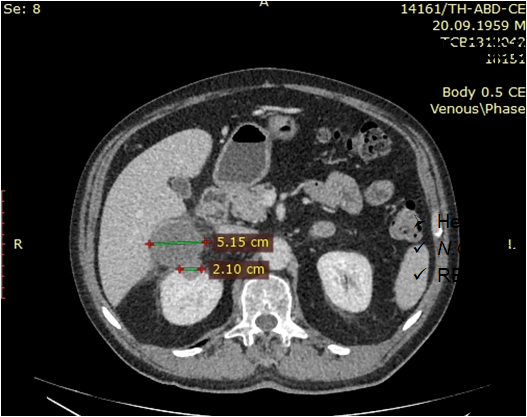

Під час проведення профілактичного УЗД у нього було виявлено пухлину правої нирки.

Основний: T-r (2 пухлини) правої нирки сT2 N0 M0 Gх ст ІI, кл.гр 2.

Супутній: Кісти нирок.